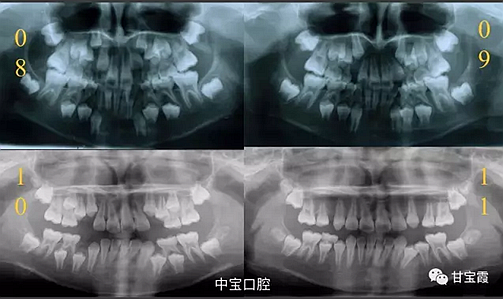

經(jīng)過我臨床檢查和X線的診斷,決定早期干預,每三個月定期復診檢查一次,并拔掉了幾個乳牙和四個恒牙,正畸專業(yè)叫序列拔牙。

5.png

這個故事告訴我們,只有家長早點把孩子帶給正畸醫(yī)生檢查,才能早期發(fā)現(xiàn)早期治療。起到了事半功倍的效果。矯正以后還不容易復發(fā),因為從08年的初診到11年戴矯正器這三年多的時間里,孩子的牙齒是自己長好的。